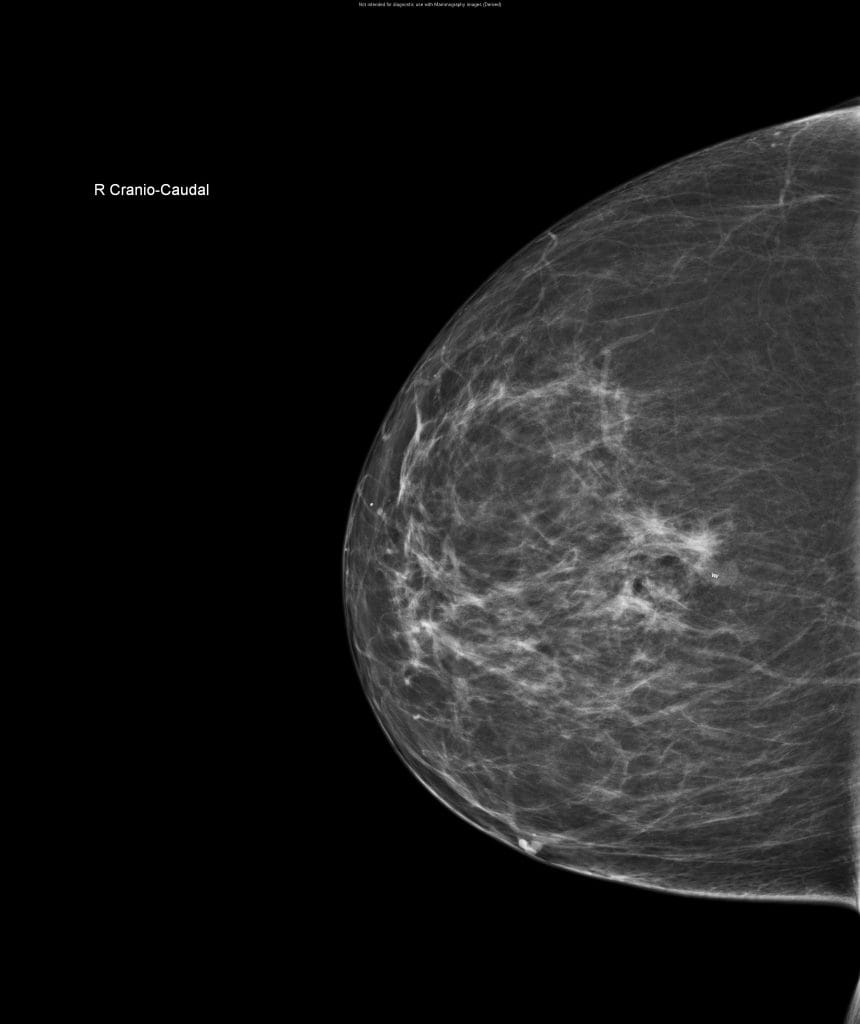

CESM is an advanced form of mammography that uses a safe dye injected into the bloodstream. This dye highlights areas of concern within the breast, giving clinicians a much clearer and more detailed image than a traditional mammogram.

“Sometimes it can be difficult to interpret a mammogram, especially in patients with dense breast tissue”, Nicole explains. “It’s a bit like looking for a cloud in a sky full of clouds. The contrast helps remove that ‘noise’ and shows us exactly what’s going on inside the breast.”

Breast Unit Consultant Shama Puri explains the impact CESM has had within the department so far: “CESM has enhanced patient care by providing us more accurate information and increasing the sensitivity for detecting breast cancers, especially in dense breasts. It is providing us with functional information similar to MRI but at lower cost and easy accessibility within the breast clinic leading to faster diagnosis and avoiding treatment delays. Thank you to Derby & Burton Hospitals Charity and their supporters for funding this technology.”